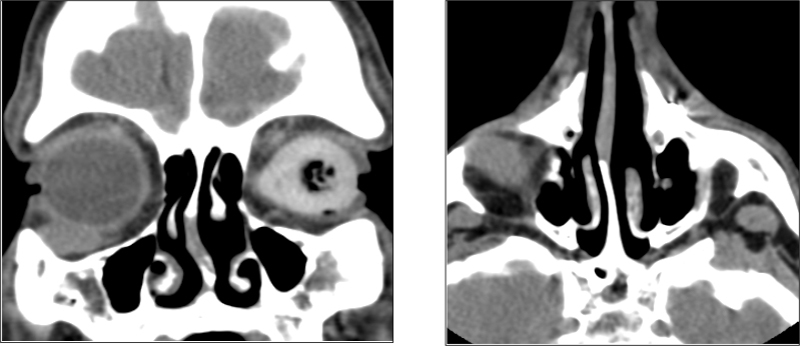

La TAC orbitaria identificó una tumoración ovalada de 6,8x13, 3x14, 1mm, en región supero-externa del globo ocular derecho de una densidad similar a partes blandas, con aspecto moderadamente heterogéneo sugestivo de proceso expansivo (Figura 1). Dados los antecedentes patológicos del paciente y el crecimiento agudo de la lesión se decidió realizar biopsia excisional (Figura 2). La tumoración era de un tejido elástico con límites mal definidos. No invadía los músculos recto inferior, ni recto lateral y respetaba el globo ocular (Figura 3). El material obtenido se etiquetó de sarcoma fusiforme grado 3. Dada la baja supervivencia de esta entidad, se valoró conjuntamente con el comité de oncología y se decidió plantear cirugía radical: exanteración. El paciente rechazó la misma y siguió controles posteriores. Ocho meses después el paciente seguía libre de enfermedad con estudio de PET-SCAN negativo.

Figura 2. Biopsia excisional con abordaje subciliar. Tejido elástico, límites mal definidos. No invade recto inferior ni recto lateral y respeta el globo ocular